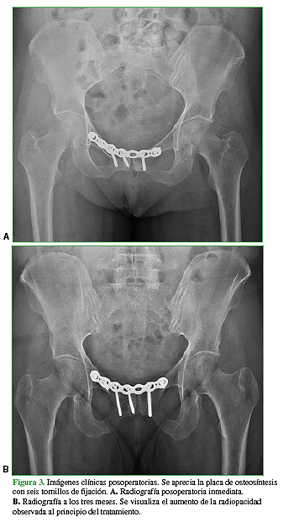

Luego de discutir el diagnóstico y las opciones terapéuticas con la paciente, se decidió realizar una osteosíntesis de la sínfisis del pubis con una placa de reconstrucción de huesos planos de acero inoxidable de 3,5 mm (Stryker® Trauma) y seis tornillos corticales autorroscantes de 3,5 mm (Figura 3). Se logró una fijación estable y no hubo complicaciones técnicas para su aplicación. La paciente comenzó con terapia de rehabilitación a los 15 días de la cirugía, y evolucionó favorablemente, con mejoría progresiva del dolor hasta la remisión completa a las 12 semanas de la operación. A los tres meses, comenzó con gimnasia y, a los seis meses, retornó a la actividad deportiva, sin síntomas.